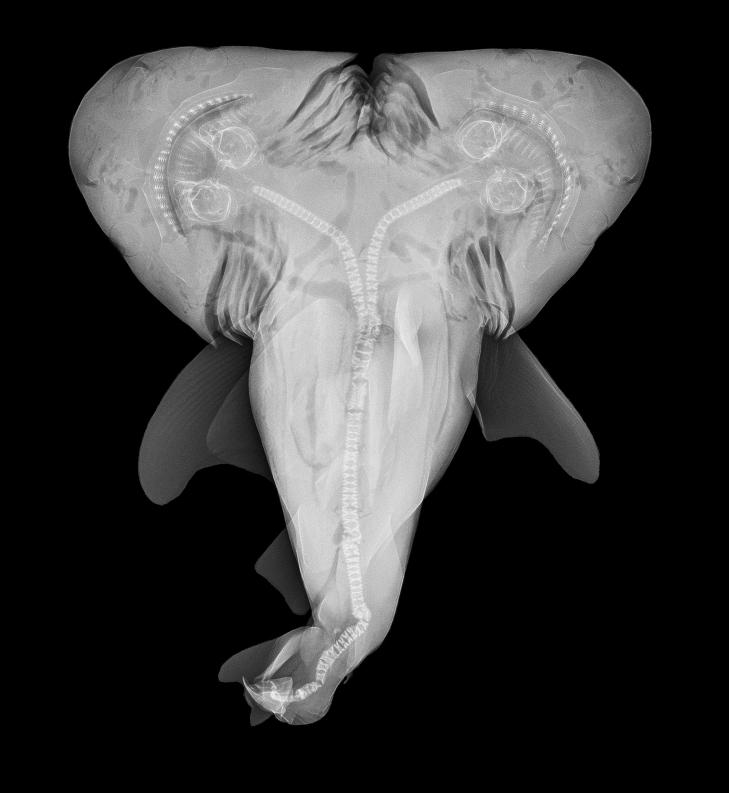

INNSYN: Et MR-bilde av haifosteret viser at det har adskilte hoder, hjerter og mager. Foto: Patrick Rice / Shark Defense / Florida Keys Community College

MR-bilder av dyrets indre avslører adskilte hoder, hjerter og mager. Resten av kroppen går sammen mot midten og ender i en felles hale. I motsetning til siamesiske tvillinger, som er to sammenvokste individer, er dette ett enkeltindivid med dobbelhode, sier førsteamanuensisen.